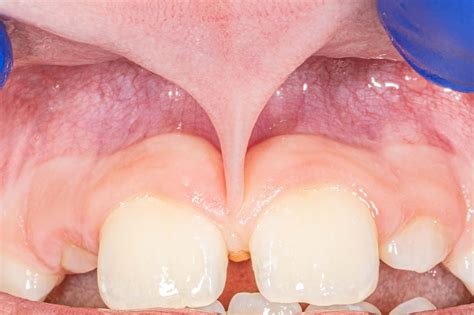

In the mouth, the frenulum is a small piece of tissue that connects the tongue to the floor of the mouth, or the upper lip to the gum. A frenectomy may be necessary in cases where the frenulum is too short or too tight, causing discomfort or difficulty with speech or eating.

A frenectomy is typically performed under local anesthesia and involves making a small incision in the frenulum to release it. The procedure is usually quick and relatively painless, with minimal recovery time required.